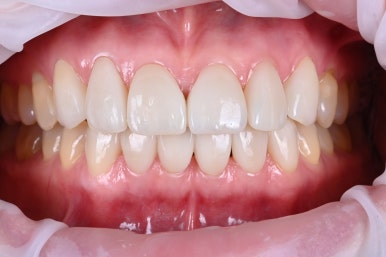

Before & After

모든 작품은 Before & After로 비교되어야 확실하게 확인할 수 있습니다.

전과 후의 사진이 진짜 같은 사람인가..? 싶을 정도로 드라마틱한 변화를 보여주고 있습니다.

살짝 웃는 모습을 보았을 때, 더 확연히 라미네이트 치료의 효과가 보이는 것 같습니다.

어떠신가요? 오랫동안 여러번에 걸쳐 치료받았던 앞니 레진의 변색과 치아 벌어짐에서 자유로워지고, 이제는 더 자신감있게 미소를 지으실 수 있을 것 같이 않나요?